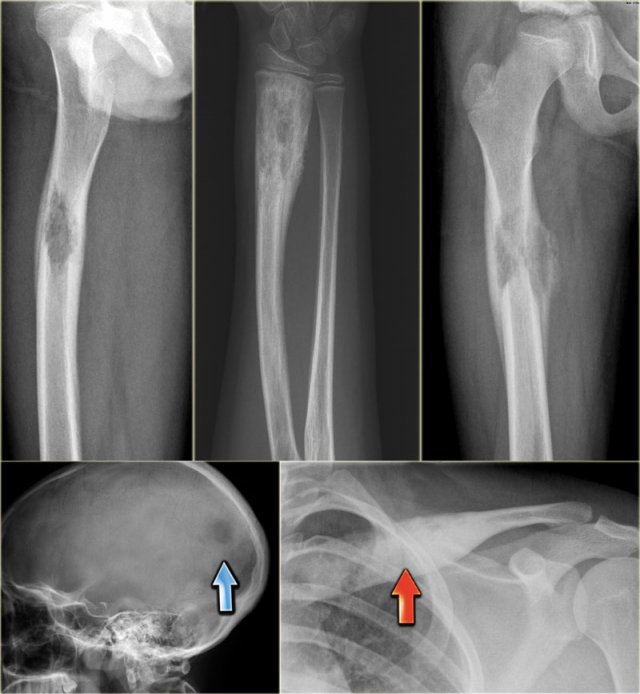

Various presentations of eosinophilic granuloma Various presentations of eosinophilic granuloma

Eosinophilic granuloma (2)

Here some examples of EG demonstrating the various more or less aggressive presentations as ill-defined osteolytic lesions (blue arrow) and even as a less common sclerotic lesion (red arrow).

Monostotic and polyostotic eosinophilic granuloma in the skull Monostotic and polyostotic eosinophilic granuloma in the skull

Eosinophilic granuloma (3)

On the left a well-defined osteolytic lesion.

A zone of sclerosis can be seen surrounding the lytic lesion.

Sometimes a so called button-sequestrum is found in the central part.

The case on the right shows multiple ill-defined lesions in the parietal and frontal bone.

Histology revealed eosiniphilic granuloma.

In a young child with multiple lytic lesions of the neurocranium EG is the most likely diagnosis.